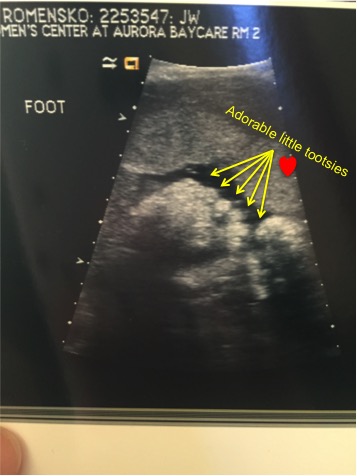

- At my last ultrasound, they took the below alarming photo of the baby. I mean, does he not look like the angriest baby you’ve ever seen? So that gave me anxiety 😳